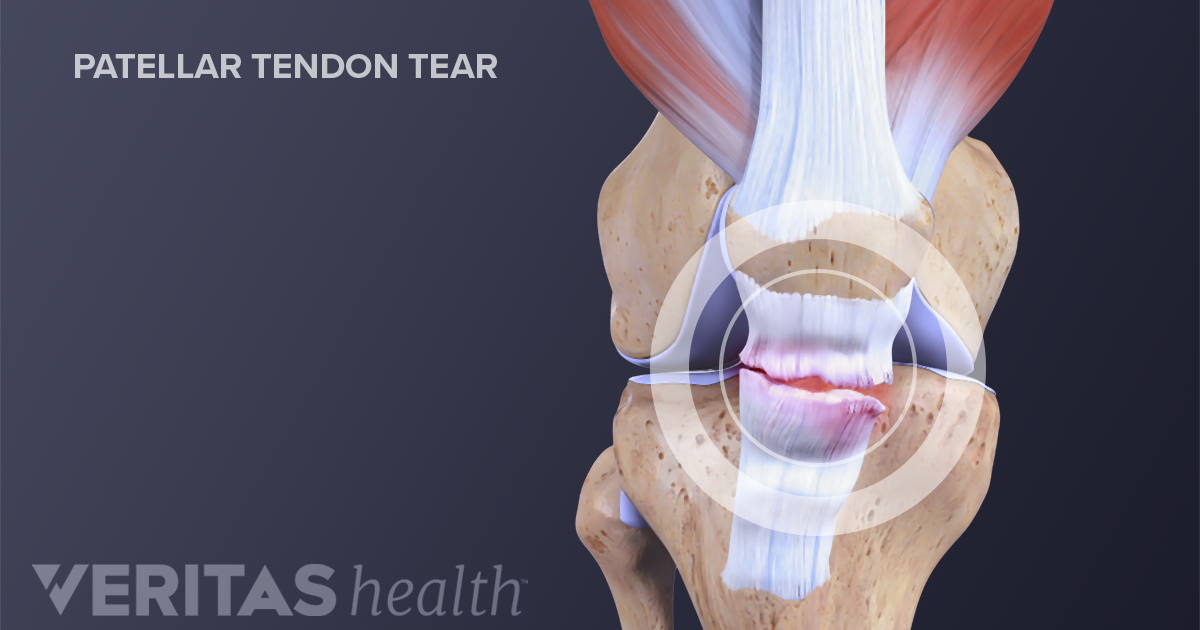

Patellar Fractures (Broken Kneecap

Patellar Fractures (Broken Kneecap